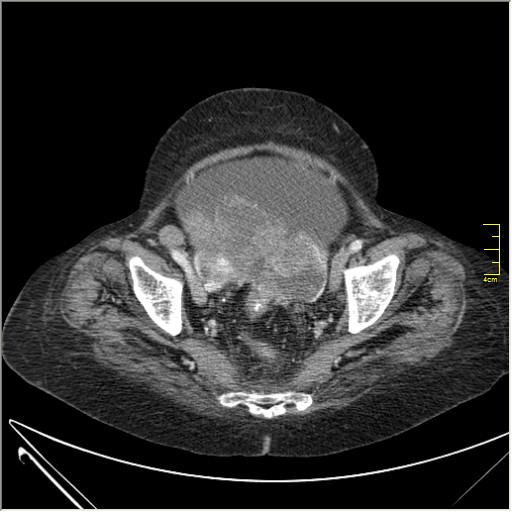

Женщина 72 года. Поступила с жалобами на вздутие живота. После осмотра хирургом, была сразу направлена на КТ брюшной полости.

Как мнение начинающего в КТ: на мой взгляд на серии томограмм определяется обьёмное образование органов малого таза, если так то - лапароскопия.

Итак, асцит с объёмным образованием таза. В данном случае можно быть более конкретным, у пациентки неоплазия правого яичника с региональной лимфаденопатией (увидели?) и выраженным асцитом, характерным именно для злокачественных опухолей яичников. Пациентка оперирована ( операция Вертгейма); диагноз верифицирован: аденокарцинома правого яичника (серозная). Направлена к онкологу для дальнейшего лечения.